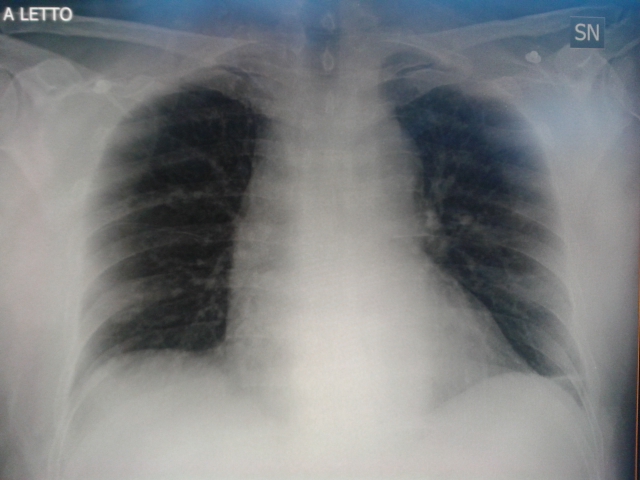

Placato il dolore, gli fai eseguire in RX torace. Lo fa da disteso. E’ stata appena fatta della morfina, è ancora un po’ sofferente, non ci fidiamo a farlo alzare. Forse se l’avesse fatto da in piedi, magari anche con proiezione laterale, ci avrebbe detto di più, o forse (e probabilmente) no. Comunque date un occhio alla radiografia del torace e giudicate voi. Ora PA 190/100. Altri 20 mg labetalolo. Prosegui con boli di labetalolo ev. Si monitorizza il paziente continuando a correggere i valori pressori e a controllare il dolore. PA 140/90.